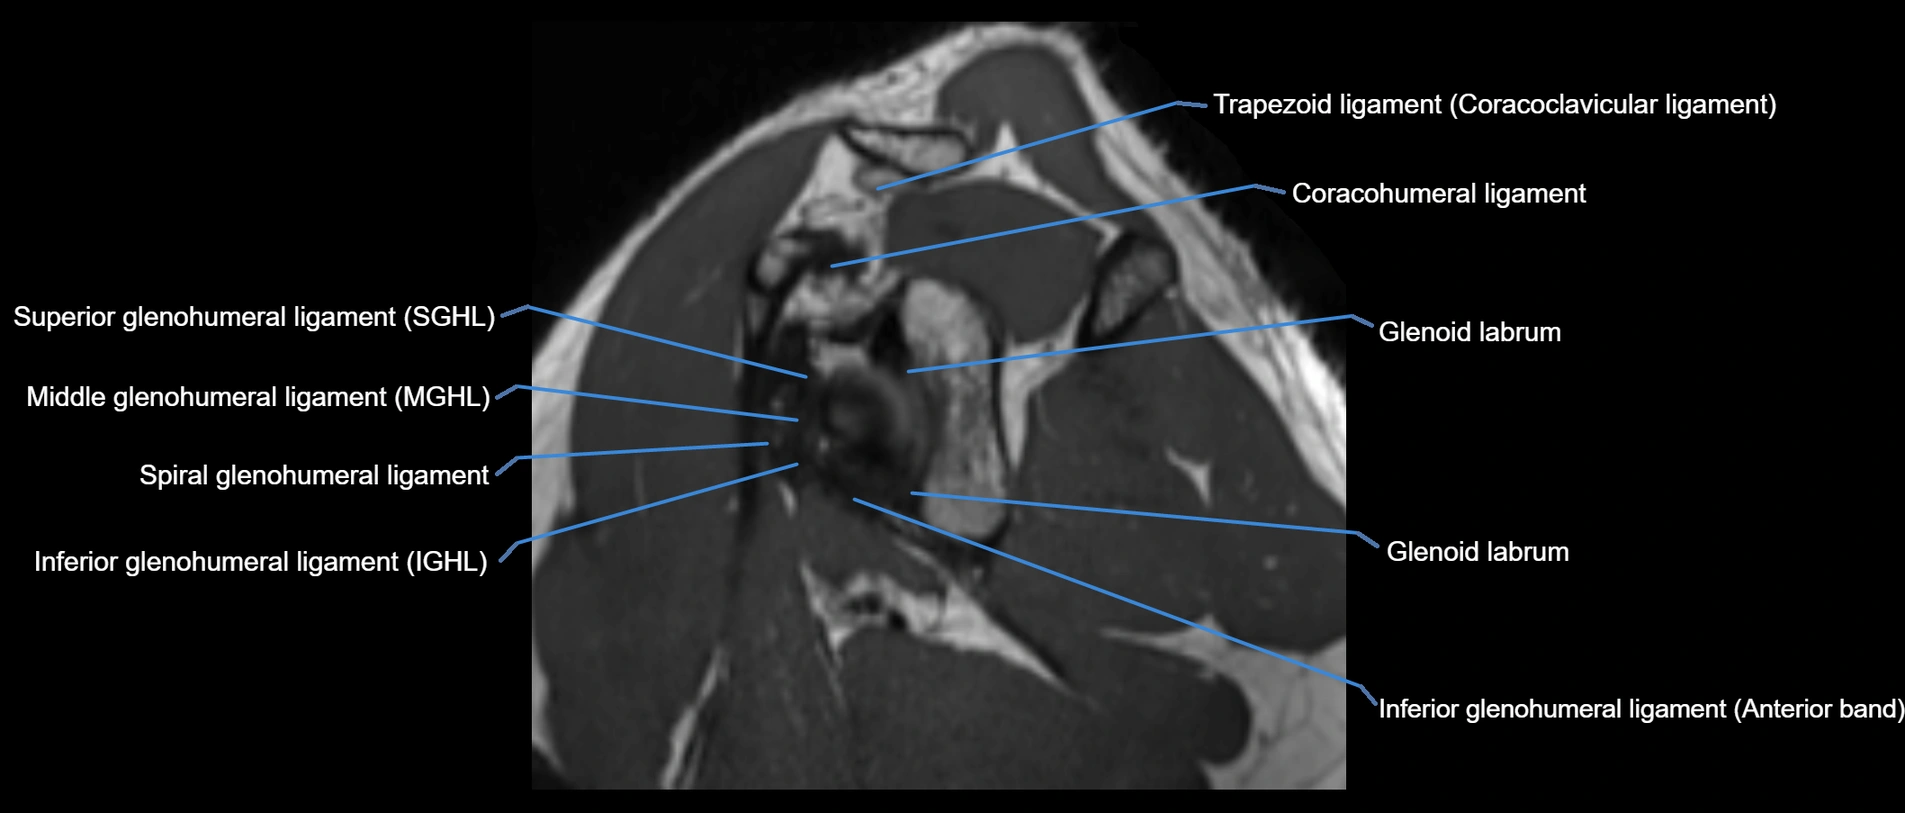

MRI images

image

MRI Appearance

• T1-weighted images:

• Normal ligament: Low signal (dark linear band) spanning acromion to clavicle.

• Surrounding fat planes: Bright, delineating the ligament clearly.

• T2-weighted images:

• Normal ligament: Low signal, homogeneous.

• Partial tear or sprain: Focal hyperintensity or thickening.

• Complete tear: Discontinuity with fluid-bright gap between clavicle and acromion.

• STIR:

• Normal ligament: Dark linear band.

• Injury or inflammation: Bright hyperintense signal in and around ligament fibers.

• Highlights periligamentous soft-tissue edema, especially in acute trauma.

• Proton Density Fat-Saturated (PD FS):

• Normal ligament: Low signal, uniform thickness.

• Partial tear or sprain: Bright signal or contour irregularity.

• Complete tear: Clear discontinuity with bright signal gap and joint effusion.

• Excellent for assessing joint capsule, coracoclavicular ligaments, and periarticular edema.